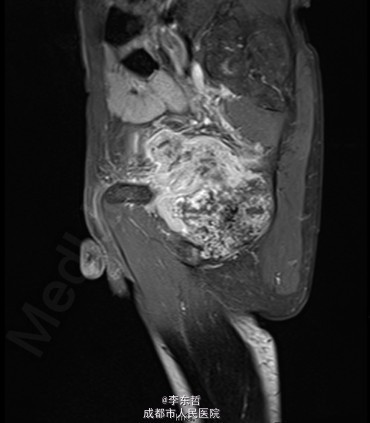

查体:臀部、会阴部、下腹部未触及包块,左下肢前内侧皮肤感觉较对侧减弱,双侧膝反射、跟腱反射正常引出,肛周皮肤感觉减退,直肠指检可触及质韧包块,活动度较差。双下肢肌力5级,双下肢各关节活动度可。 辅查:外院增强CT示:盆腔左侧壁见团块状软组织密度影,密度不均,其内见多发斑块高密度影,病灶大小约9.4*7.6cm,增强后强化不明确。我院X片示:左侧闭孔及耻骨区见不均匀高密度影,大小约6.2*6.7cm。我院MRI示:盆腔左份见长T1长T2肿块影,大小约10.3*7.7*10.5cm,向前推挤膀胱,向右推挤前列腺。我院骨扫描显示:耻骨联合及左侧耻骨支核素浓集。